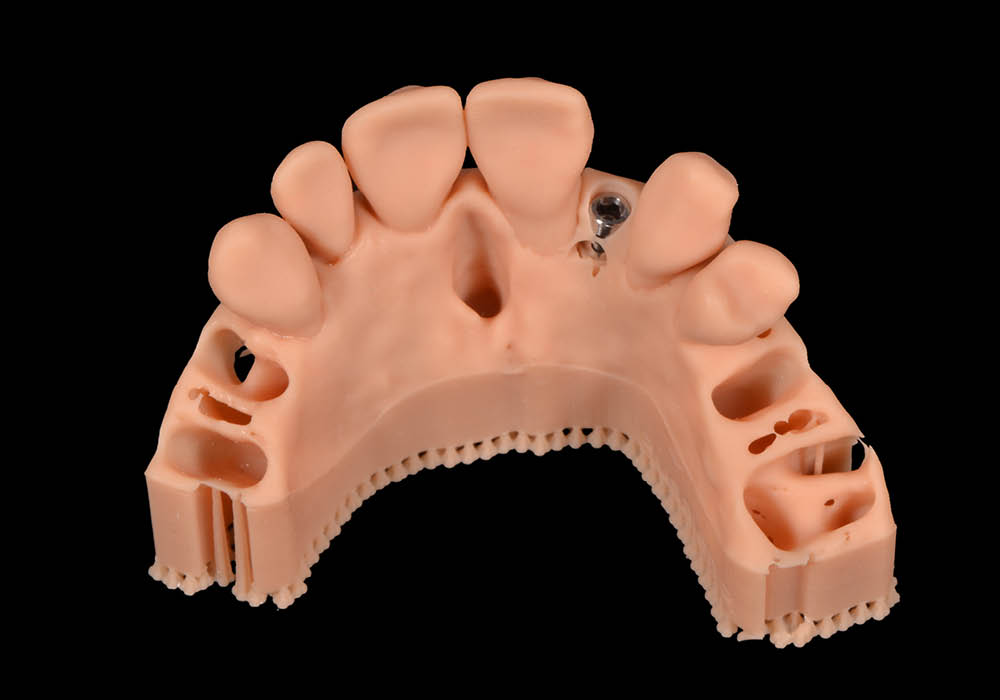

4. Esportazione dei file STL

Una volta confermata la posizione implantare, i file sono stati esportati in formato STL per le successive fasi di modellazione e costruzione dei dispositivi ausiliari.

5. Costruzione del tappo di guarigione in PEEK

Su misura per la paziente, è stato realizzato un tappo di guarigione anatomico in PEEK, progettato per guidare correttamente la guarigione dei tessuti molli e mantenere il profilo di emergenza ideale in funzione del futuro restauro.